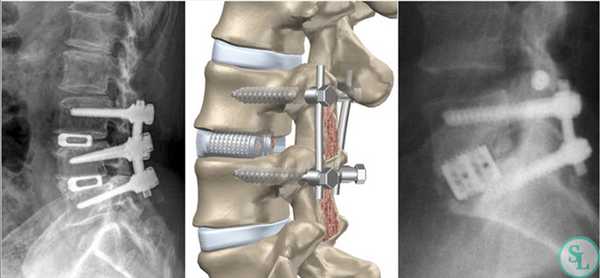

Жесткие стабилизирующие системы

Системы жесткой фиксации подразумевают установку в межпозвонковое пространство костного трансплантата (обычно взятого из подвздошной кости пациента) или специального искусственного кейджа с последующим монтажом на два и более соседних позвонка металлической конструкции. В результате они обездвиживаются и со временем сращиваются между собой, т. е. происходит спондилодез.

Жесткая стабилизация подразумевает использование техники транспедикулярной фиксации или транскутанной стабилизации. Они очень похожи между собой и отличаются одинаковой эффективностью, но последняя обладает лучшим косметическим эффектом, поскольку все манипуляции осуществляются через точечные проколы мягких тканей.

Суть метода состоит в применении специальных титановых винтов и пластин. Винты вкручиваются в точку пересечения поперечных отростков позвонка с суставными по обеим сторонам позвонка. Таким образом, фиксируется минимум 2 позвонка, хотя в ряде ситуаций требуется стабилизация значительного большего количества позвоночно-двигательных сегментов. Через шляпки винтов пропускают титановую пластину, обеспечивающую жесткость конструкции и распределение нагрузки на нее.

Стабилизационная система на рентгене.

В большинстве случаев проблемный сегмент стабилизируют с помощью металлоконструкций, чаще представленных транспедикулярными системами и пластинами с винтами из высокотехнологичных сплавов металла. В хирургии такая техника называется инструментацией позвоночника. Кроме металлоконструкций, для стабилизации также могут быть применены полимерные устройства, сделанные, например, из углеводородного волокна или резорбирующегося высокомолекулярного биополимера. К отдельной разновидности стабилизирующих вмешательств, которые не причисляют к инструментации, относят установку кейджей имплантатов межпозвоночных дисков.

Кейджы межпозвоночных дисков поясничного отдела.

В преобладающем количестве подобные операции заключаются в достижении полного обездвиживания патологических уровней за счет прочного скрепления двух или более позвонков ригидными конструкциями. Это позволяет позвонкам с течением некоторого времени (от 3 до 6 месяцев) срастись между собой и образовать единый неподвижный костный блок. То есть, на прооперированном поле подвижность между позвонками будет заблокирована, а человек сможет нормально двигаться и ходить, не испытывая при этом боли и прочих неврологических расстройств.